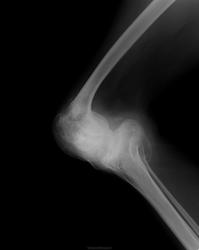

Заключение Главного детского хирурга ДЗ г.Москвы от 02.04.2007 года: Сирингомиелия. Патологический перелом Л2. Кифотическая деформация позвоночника. Радикуломиелопатический синдром. Врожденная сенсорная нейропатия с ангидрозом и спонтанным ангиолизисом. Вальгусная деформация правого коленного сустава на почве остеолизиса дистального мыщелка бедренной кости, нестабильность коленного сустава справа. Плоско-вальгусные стопы.

В неврологическом статусе: Сознание ясное, контактна, ориентирована. Менингеальных знаков нет. Умеренное когнитивное снижение. Несколько эйфорична. Речь дизартричная (неправильный прикус). ЧМН: без патологии. Парезов не определяется. Сухожильные и периостальные рефлексы с рук низкие, без разницы сторон. Коленные и ахилловые отсутствуют. Четких чувствительных нарушений не выявлено. Гипотрофия мышц верхних и нижних конечностей, ягодиц. Грубая деформация правого коленного сустава с формированием ложного сустава, отведением правой голени кнаружи под углом 30-40 град, деформация костей стоп, эквинус с 2-х сторон. Укорочение правой ноги на 15см. ходит с опорой на «мыски». Кифоз шейного отдела. Грубый кифоз поясничного отдела с формированием горба. Сколиоз. Мышечный тонус в верхних конечностях не изменен, в нижних конечностях сни жен, больше справа. Гипермобильность в правом тазобедренном суставе. Тазовые функции: не нарушены.